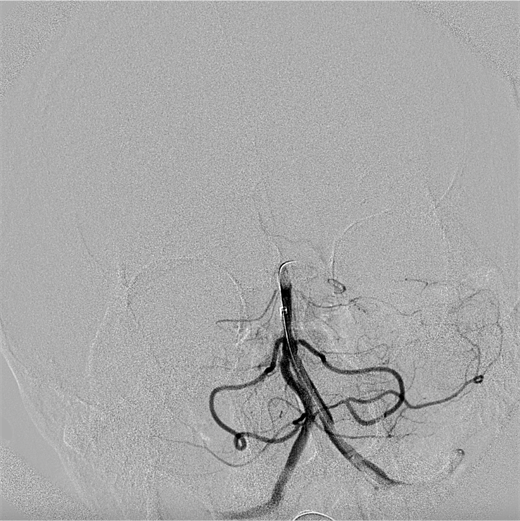

手术中,神经内科三病区主任张振昶取栓团队急诊实施了全麻下脑血管造影术和经导管颅内血管血栓去除术,从股动脉穿刺到血流复通仅用时13分钟,顺利取出1枚大小约3mm*6mm的暗红色血栓。术后,患者逐渐清醒,四肢可自主活动,经神经内科ICU的精心监护、高效治疗,术后第三天患者意识完全恢复正常,肢体活动自如,mRS评分0分,已具备回归正常工作生活的能力,全体医护人员精湛的医疗技术和精心的护理获得了患者和家属的一致好评。

术前